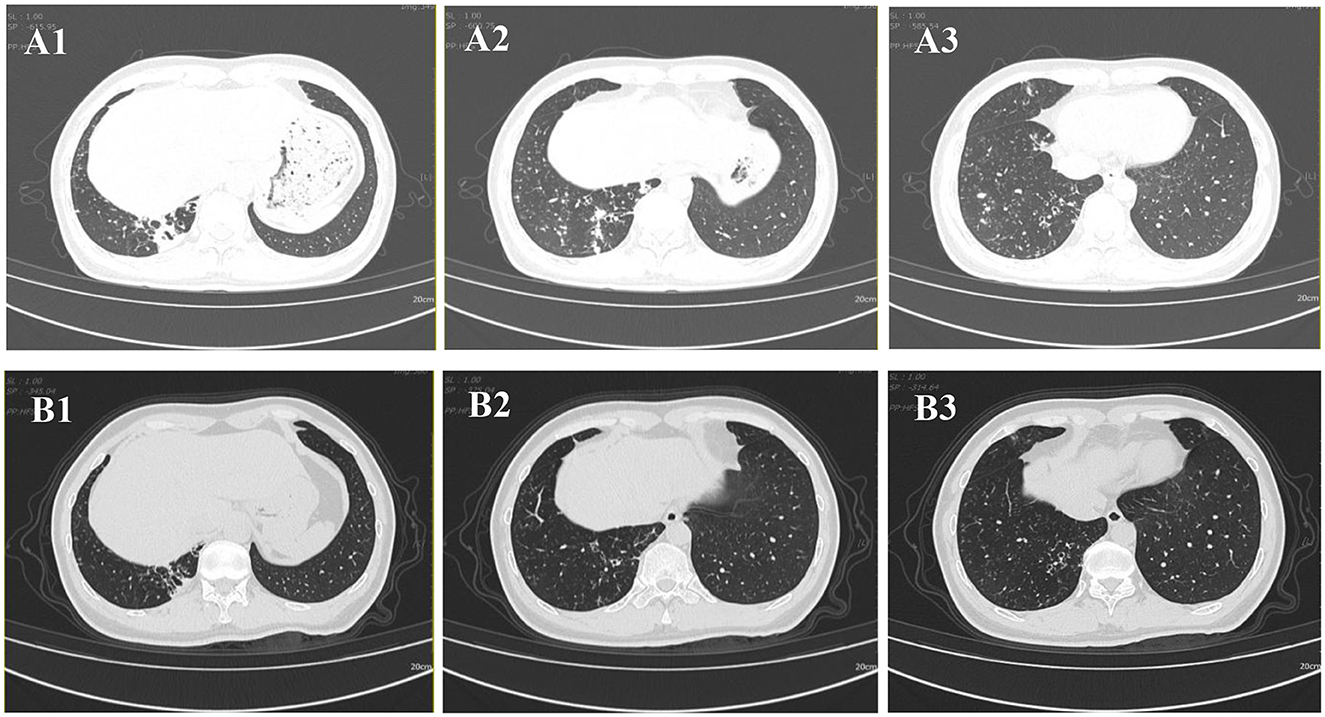

Chest CT imaging, however, demonstrated significant pathology, revealing bronchiectasis in the medial segment of the right middle lobe and the right lower lobe. These areas were accompanied by multiple surrounding patchy opacities and nodules, suggestive of bronchiectasis with superimposed infection (Figures 1 A1A3).

Figure 1. Chest CT images. (A1–A3) CT scan obtained on 2024-08-30 demonstrates bronchiectasis in the medial segment of the right middle lobe and the right lower lobe, accompanied by surrounding multiple patchy and nodular opacities. (B1–B3) Follow-up CT scan obtained on 2025-02-08 shows interval resolution of the peribronchial infectious foci in the right lower lobe.

Following targeted therapy, the patient's clinical symptoms improved significantly. A follow-up chest CT on February 8, 2025 (Figure 1 B1B3), showed marked resolution of the bronchiectasis with nodules compared to baseline (August 30, 2024). Subsequent follow-up at 24 weeks (until July 2025) confirmed sustained clinical stability without relapse and no reported drug-related adverse events.

Drug therapy for NTM disease requires careful consideration due to the diversity of NTM species and their varying drug susceptibility profiles. Current guidelines strongly recommend performing in vitro DST before initiating treatment (35). The regimen should include at least two drugs likely or known to be effective against the specific NTM isolate; severe cases may require 4–6 effective drugs, and monotherapy must be avoided (36, 37). Our DST results demonstrated susceptibility to clarithromycin and rifampicin but resistance to minocycline. The subsequent successful clinical and radiological response to a DST-guided triple-drug regimen (clarithromycin, rifampicin, and ethambutol) further validates this approach (Figure 1 B1B3 vs. Figure 1 A1A3), and is consistent with treatment outcomes described in other susceptible cases (5, 24). However, a critical comparison with the broader literature reveals noteworthy heterogeneity in the drug susceptibility profiles of M. colombiense. Most notably, a contrasting case from Brazil involved an isolate exhibiting high-level resistance to both clarithromycin and rifampicin (9), which culminated in a fatal outcome despite therapy. This discrepancy underscores that susceptibility to first-line macrolides and rifamycins should not be universally assumed. Therefore, the variations in susceptibility profiles among M. colombiense isolates highlight the importance of DST (38). Guided treatment based on individual DST results remains essential for effective clinical management.